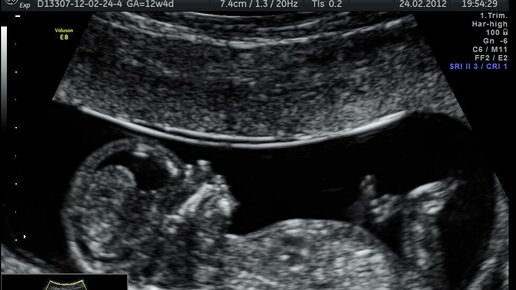

Прошло уже несколько месяцев со дня 2го скрининга и только сейчас я собралась с силами написать о тех днях. Надо было все осознать, принять и пережить. На скрининг я шла воодушевленная. Ведь по итогу 1 скрининга все риски сняли, меня заверили, что у ребенка все хорошо. Каких-то плохих предчувствий и мыслей не было. Сначала на узи все шло как обычно. Называли какие-то цифры и сверяли с табличными. Я услышала несколько раз фразу "кишечник повышенной эхогенности", почему-то подумала, что это про меня (и связано с сильным газообразованием) и не придала значения. А дальше началось. Оказывается по результатам 1 скрининга не все было так радужно...

Привет, мои дорогие будущие мамочки! С вами снова наш уютный канал, где мы говорим о самом важном. Если первый скрининг уже позади, значит, вы на пороге нового, не менее волнительного этапа. Сегодня мы подробно разберем второй скрининг при беременности — что это за «зверь», когда его проходить и как не паниковать, глядя на цифры в результатах. Наливайте чай, устраивайтесь поудобнее — начинаем! Второй скрининг — это следующее плановое обследование, которое позволяет врачам оценить развитие малыша и выявить возможные риски хромосомных аномалий и пороков развития...